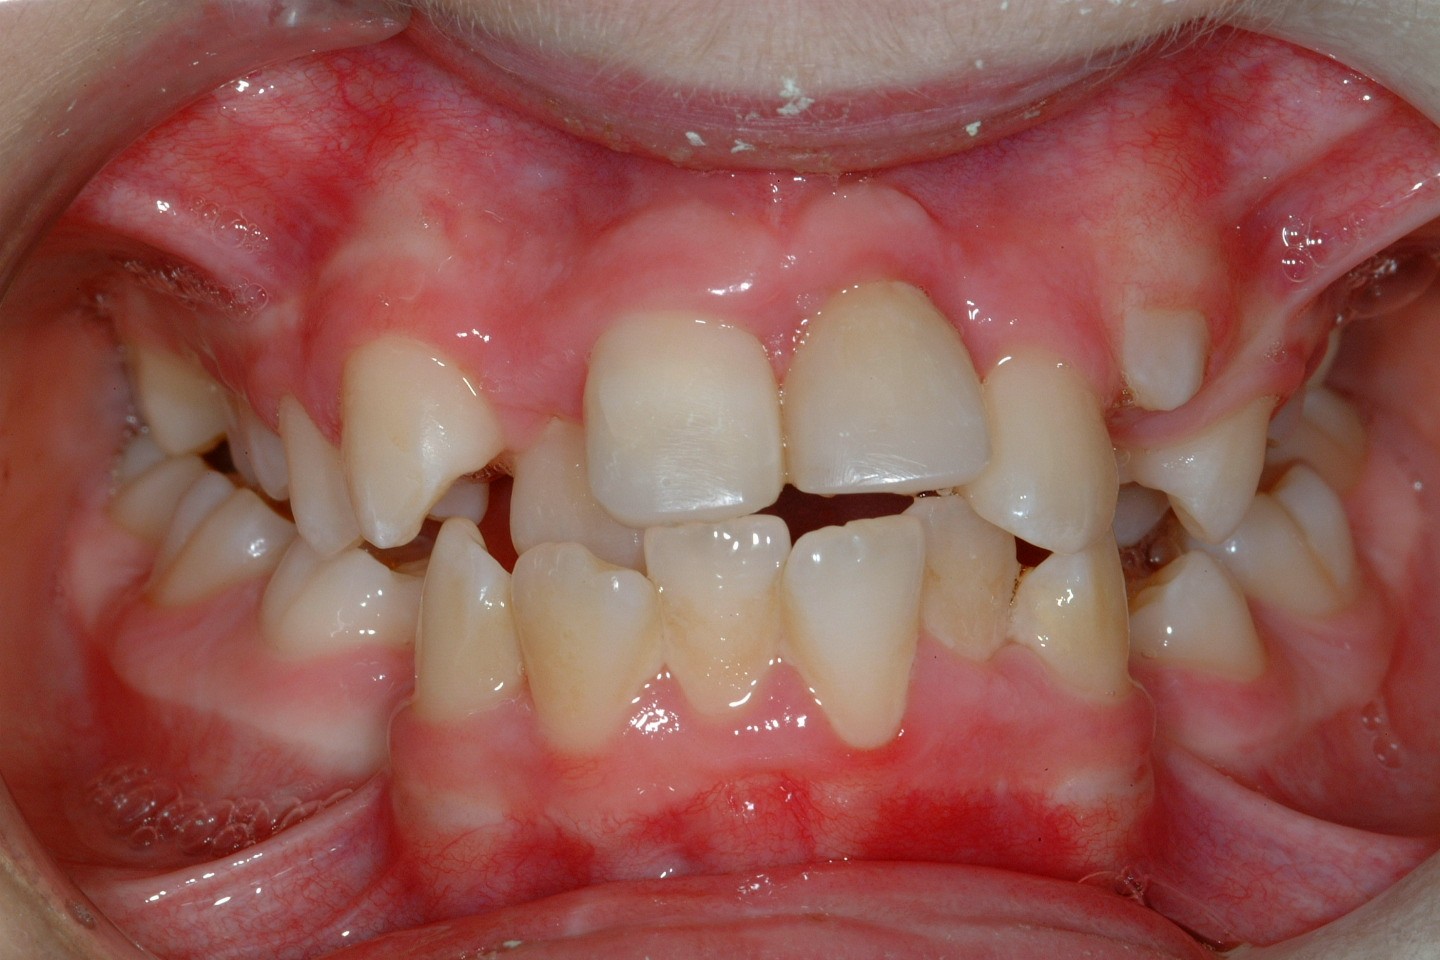

If problems with impacted or ectopic canines are identified and addressed early, chances of success are high with relatively minor interventions. If, however, the problem is not identified until later in life then other treatment options are required, frequently involving both orthodontic treatment and surgery. Treatment planning needs to take account of general factors, including issues such as patient desire, expectation and co-operation (Figure 17).